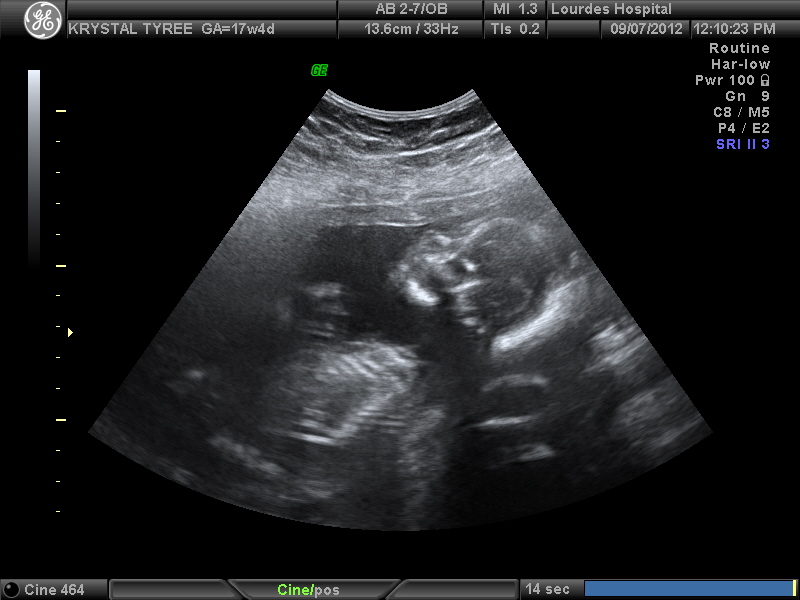

My baby at 17 weeks, I wasn't able to get any gender prediction. The baby was not very cooperative, but got a couple of profile pictures. Any guesses from the skull theory?